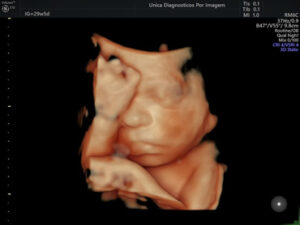

Exame importante que tem como objetivo avaliar a anatomia do feto e detectar possíveis malformações. Deve ser realizado preferencialmente realizado